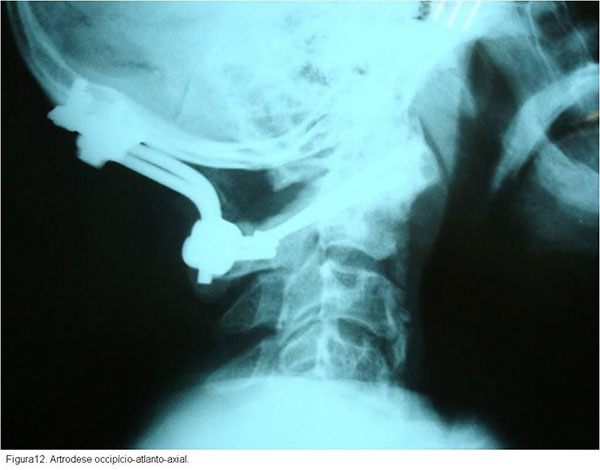

Nos casos em que houver ruptura do ligamento transverso será necessária a artrodese atlanto-axial, que poderá ser obtida após redução e imobilização inicial em halo craniano com tração, uma vez obtida estabilização da fratura pode-se passar para halo-gesso até que a fratura esteja consolidada. Após consolidação de C1, realiza-se a artodese C1-C2 para prevenir instabilidade secundária à lesão do ligamento transverso. Outra opção de tratamento seria realizar uma artrodese occipitocervical imediata, o que abrevia o tratamento, mas condiciona limitação da rotação e também da flexão (figura12).